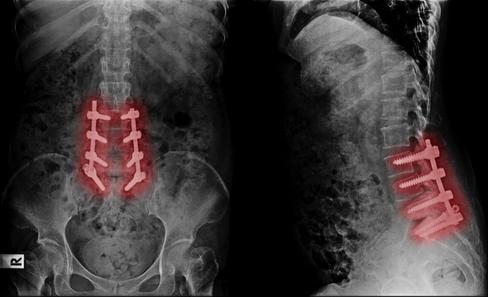

Raman Dhawan, a board-certified

orthopedic and spine surgeon, has recently joined Oswego Health’s Center for Orthopedic Care. With a wealth of experience and a strong commitment to providing exceptional local care, Dhawan will play a key role in enhancing the orthopedic services available to the community.

Dhawan brings over 18 years of experience in orthopedic surgery. After completing his orthopedic residency at Upstate Medical University from 1999 to 2004, he pursued a spine fellowship at University of California San Diego (2004-2005), where he honed his expertise in advanced spine care.

Prior to joining Oswego Health Medical Practice, Dhawan was a respected orthopedic surgeon at Crouse Hospital, where he served from 2007 until recently. Additionally, he has worked at Geneva General Hospital since 2008 and Community Memorial Hospital from 2005 to 2007.

Oswego Health Medical Practice continues to expand its orthopedic team to provide high-quality, accessible care to patients in Central New York. The Center for Orthopedic Care offers a wide range of services, from joint replacement to sports medicine care, helping patients return to their daily activities with enhanced mobility and less pain.